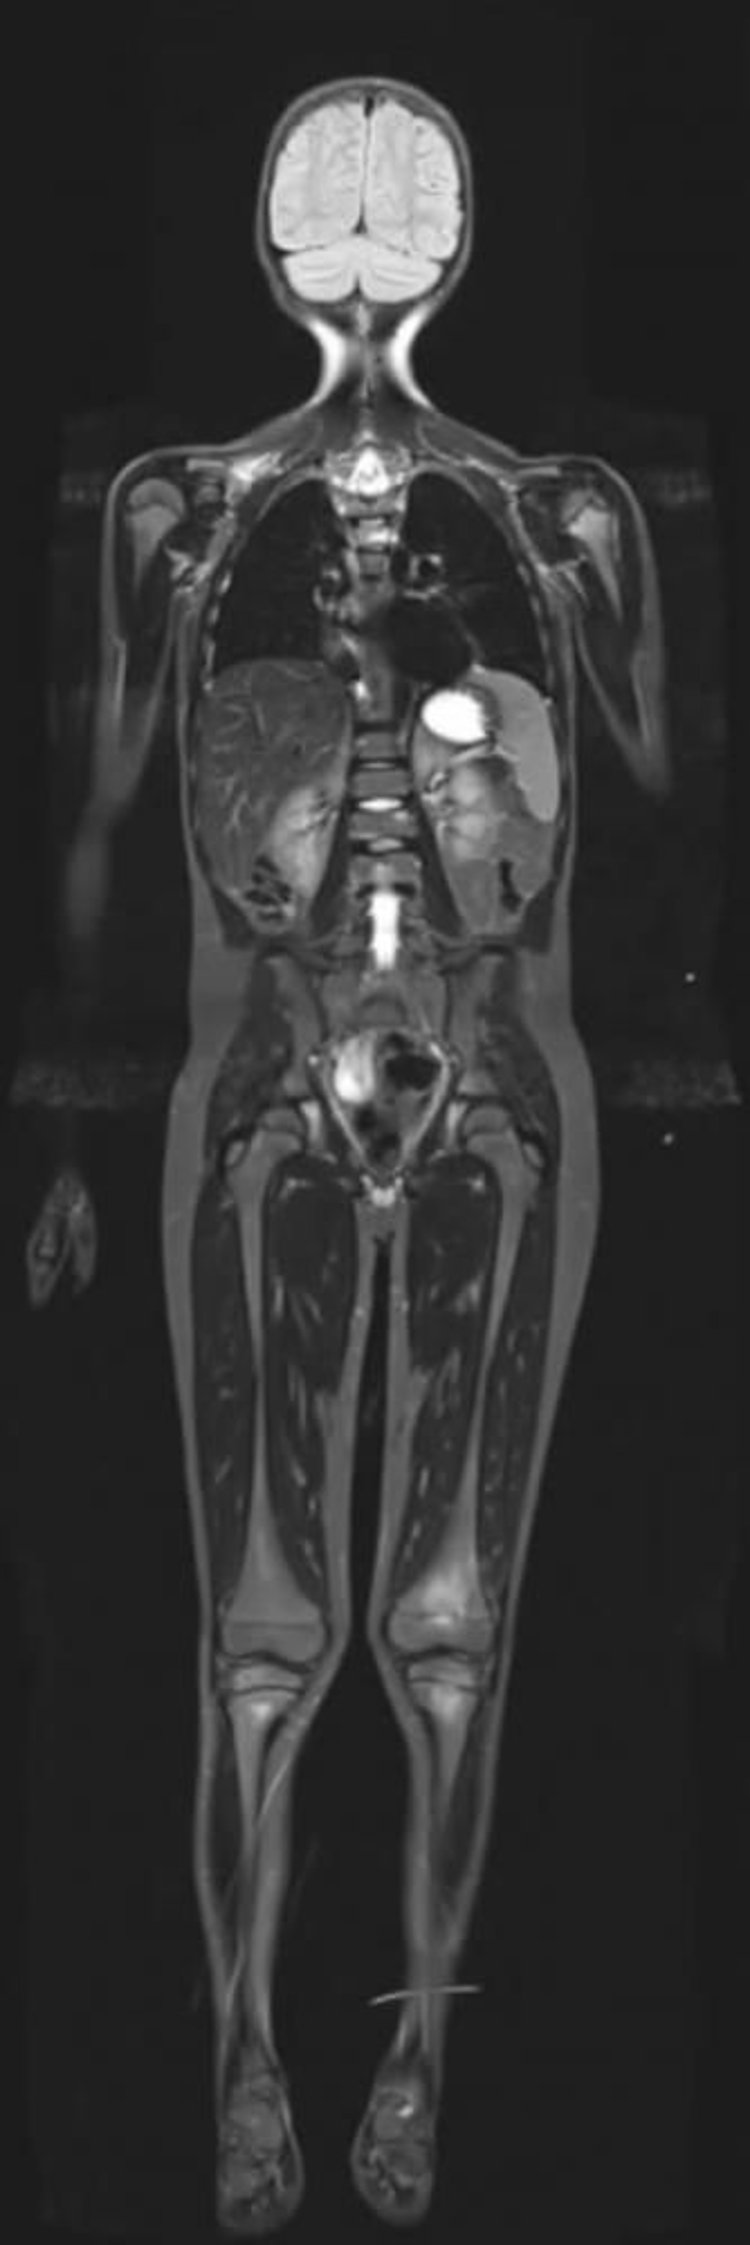

Resonancia magnética de la inversión de T1 corta (STIR MRI) del cuerpo entero

La RM de recuperación de la inversión ponderada en T1 corta puede suprimir las señales de la grasa, lo que permite el realce de otros tejidos con alto contenido de agua.

Image courtesy of Hakan Ilaslan, MD.